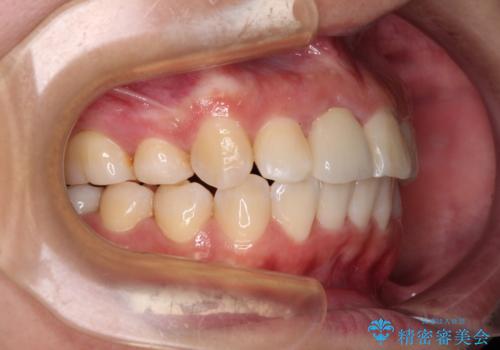

- 放置した虫歯や抜いたままの奥歯、前歯のデコボコを気にして来院された患者様です。

口元の突出感は少なく、下顎の叢生は軽微なものであったので、叢生の強い上顎左右の小臼歯を1本ずつ抜歯し、ワイヤー装置にて矯正治療を行うこととしました。

矯正治療をしたいと思っていたが、放置している虫歯が多いため、どこに相談に行けば良いのか分からずにいたそうですが、当院の総合歯科診療を見て来院されたそうです。

矯正治療中にインプラント埋入を行うなど、余計な時間や無駄のない治療を行うことができました。